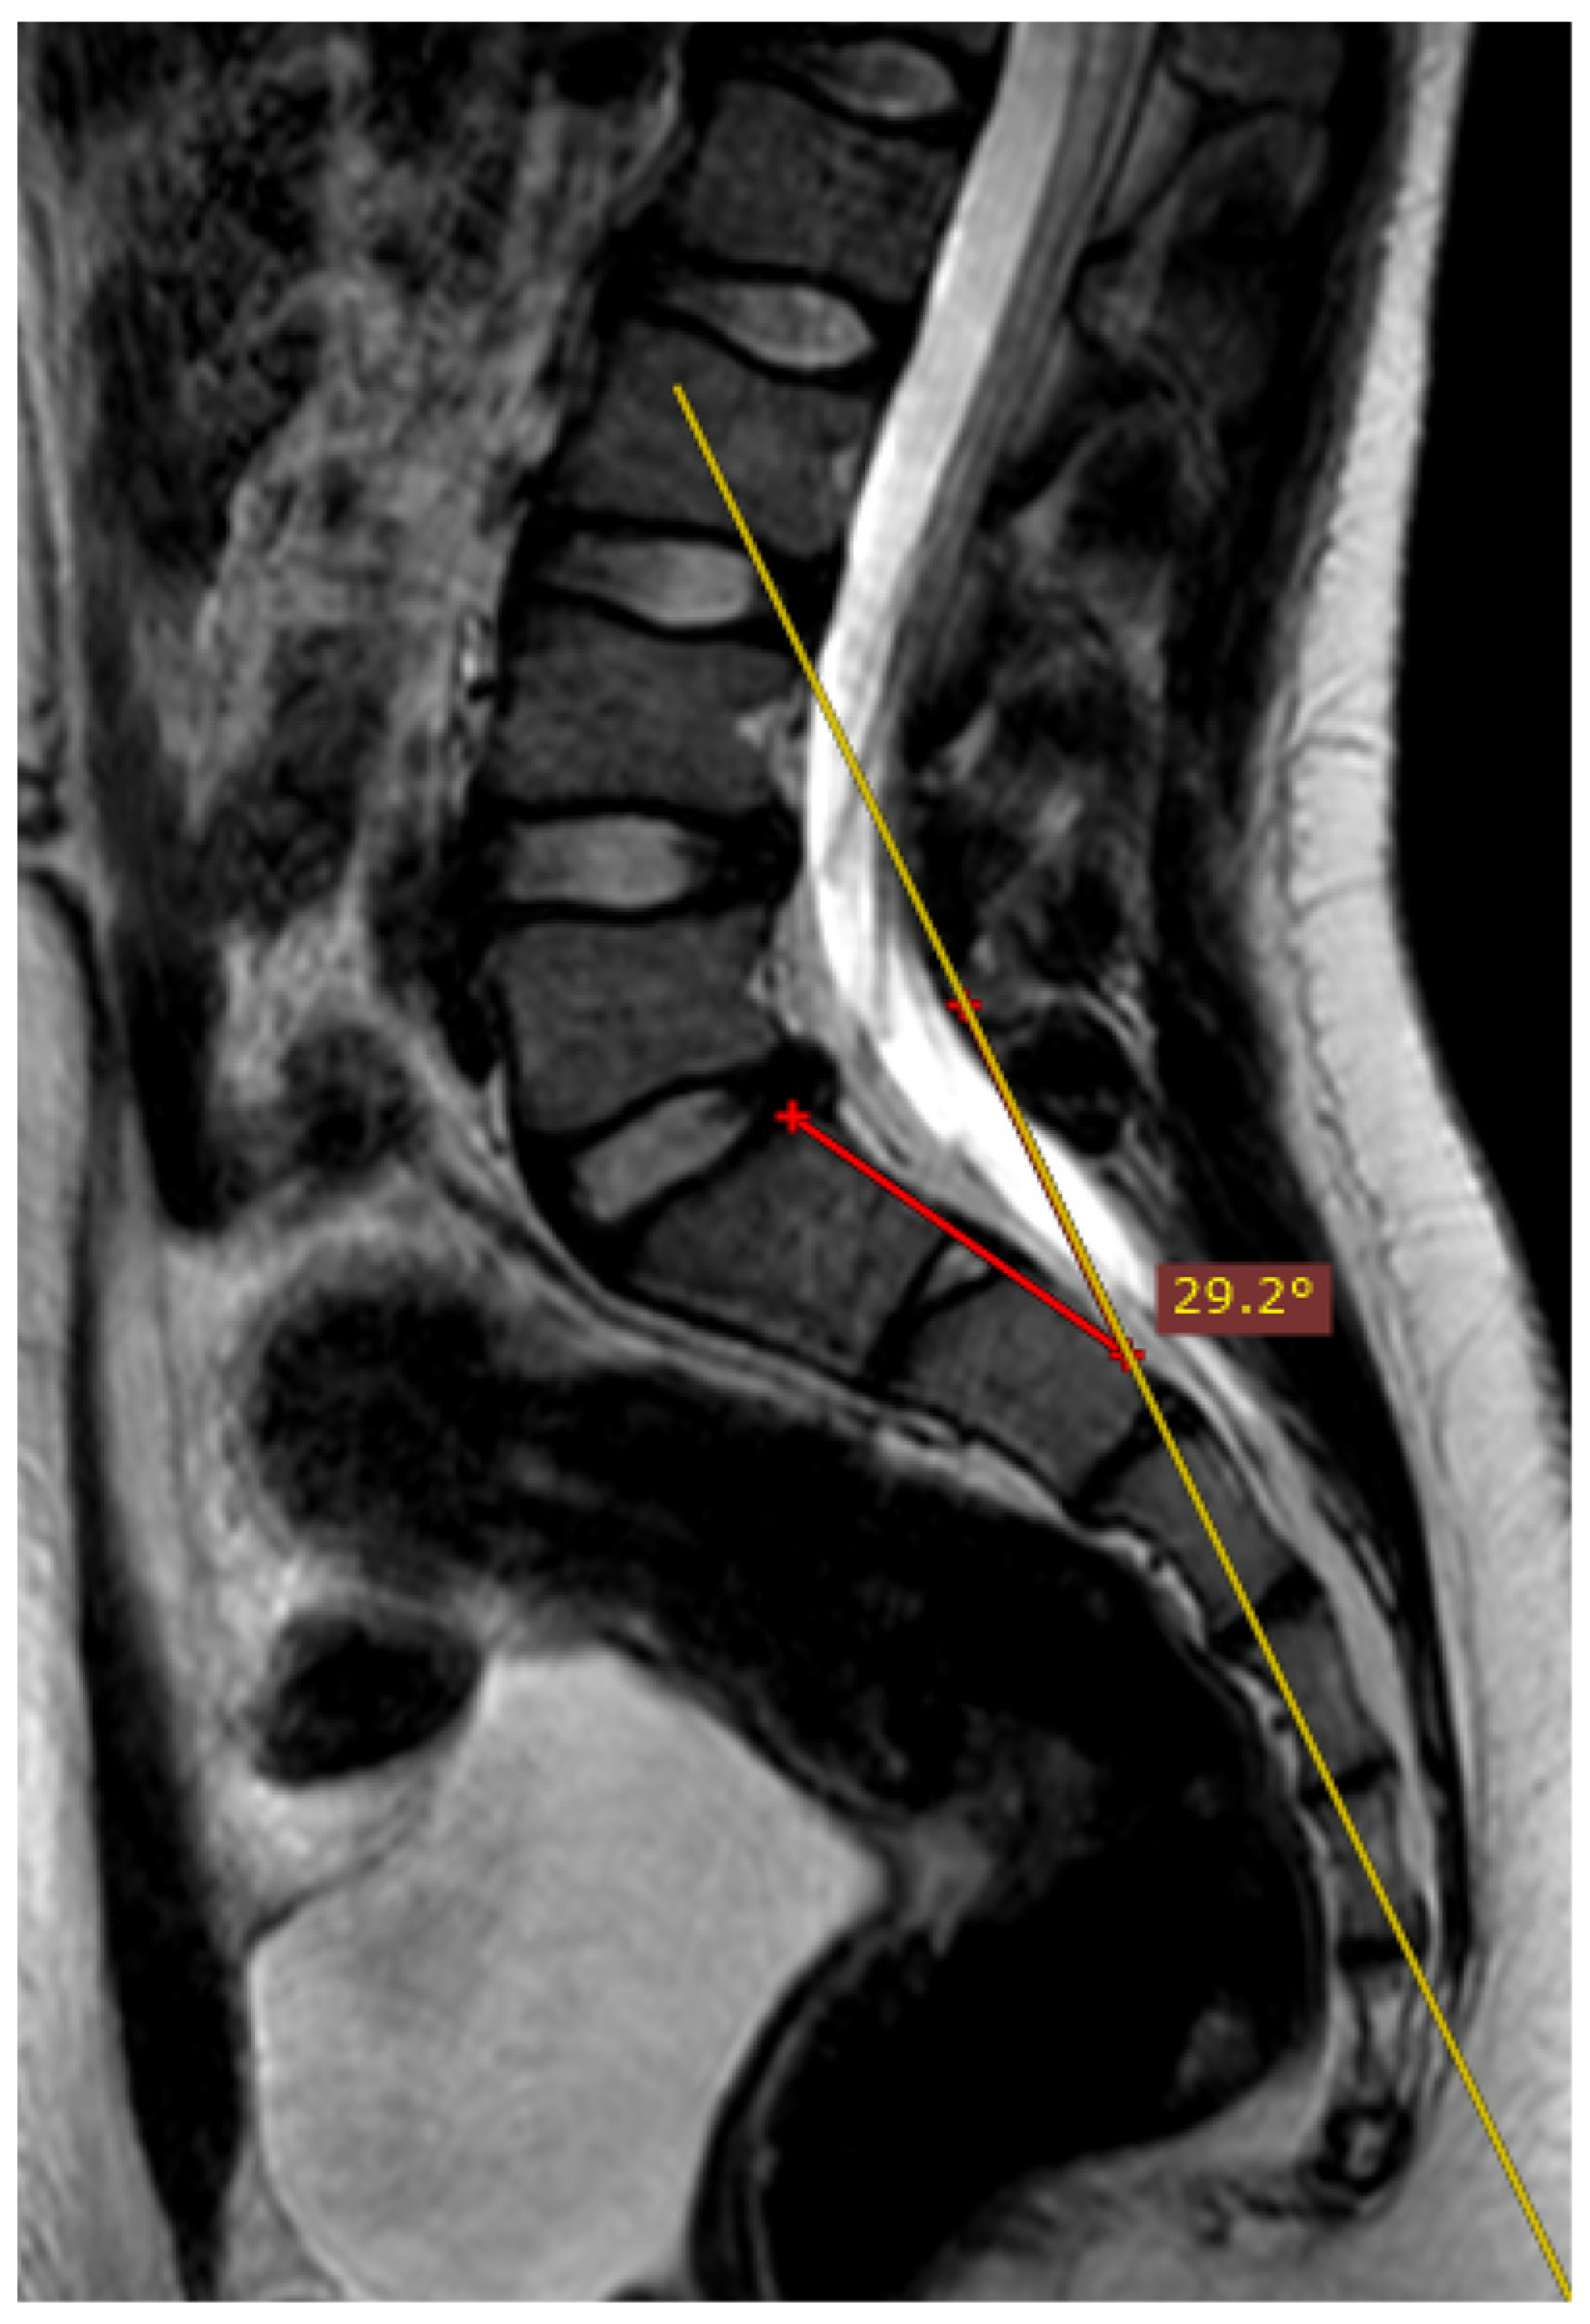

2.2.3. Manual and Automatic Segmentation of the Sacrum and Iliac Bones

In order to compare the performance of the improved algorithm depending on the technical correctness of the MRI of the sacroiliac joints, it is necessary to perform both manual and automatic bone segmentations. Therefore, it was decided to manually segment the iliac and sacral bones and then evaluate their agreement with the segmentations created by the algorithm. The area of the right and left iliac bones, as well as the sacrum, were manually labeled on consecutive slices of the T1-weighted sequence by one researcher. The segmentations were prepared manually with the 3D Slicer (version 4.11.20210226) program and then verified by two other members of the research team. After the verification, it was stated that the created segmentations cannot be more accurate and can serve as a reference for segmentations performed by the algorithm. The establishment of reference segmentation considerably simplifies the process of comparing algorithm performance, as it provides more tools that can assess the compatibility of human and artificial intelligence. The compatibility of both segmentations was evaluated by several means. Initially, to have all bone segmentations manually reviewed one by one by the researchers, a proprietary scale was introduced to assess compliance. The scale is shown in Figure 3 and was based on the SPARCC scale. In this visual scale, each examination can receive a maximum score of 48 points. Only six slices that represent the largest surface of the SIJs are selected and afterwards evaluated. Each SIJ is divided into quadrants. In each quadrant, the correspondence of manual and fully automated segmentation is evaluated; if both segmentations correspond, one point is granted. Secondly, the Dice coefficient (DC) is calculated as follows:

Figure 3.

Scoring scale used in the study. The evaluation involves six slices of each examination. (a) Graphic illustrating the division of the SIJ into quadrants: R1—right iliac (upper), R2—right sacral (upper), R3—right iliac (lower), R4—right sacral (lower), L1—left iliac (upper), L2—left sacral (upper), L3—left iliac (lower), L4—left sacral (lower). Depth and intensity rating details (SPARCC scale) are provided below the graphic. (b) Quadrant division illustrated on the T1 sequence. (c) Corresponding quadrant division illustrated on the STIR sequence.

The results of the segmentation of the sacrum and iliac bones are shown in the Table 2. The score awarded by the researcher was calculated for each examination and ranged from 0 to 48 points, with 48 points were awarded in the absence of uncertainty about the complete validity of the automatic segmentation. Fourteen percent (n = 25) of examinations were given 48 points, while the minimum score amounted to 26 points. The median of scores was equal to 47 (IQR, 5). Samples of the manual and automatic segmentations of the sacrum and iliac bones are presented in Figure 7. Kruskal–Wallis H test (H(3) = 0.512, p = 0.9162) was not statistically significant when comparing the results of the visual scale between groups, which suggests no differences in algorithm performance depending on deviation angle value.

Figure 7.

Sample slices of an average case (visual scale equal to 47, DC = 0.98): T1 sequence in the upper row, manual segmentation in the middle row and automated segmentation in the lower row.